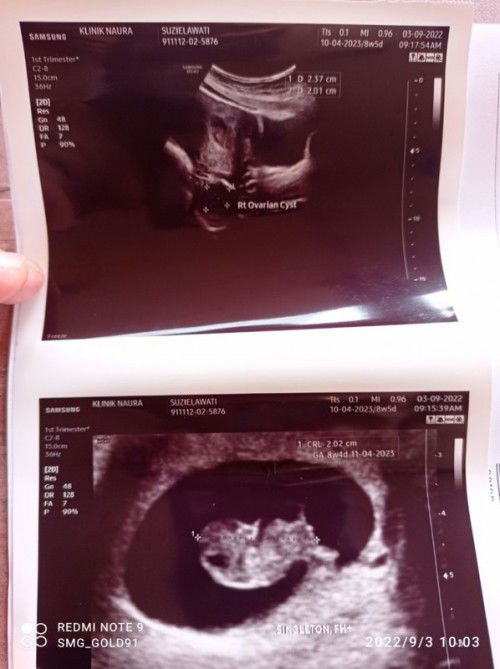

8w4d, cyst pun mengecut...rezeki tak diduga setelah 3year

Alhamdullilah dah buat scan pengesahan kehamilan. Jantung pun nampak berdetak normal . Siap nampak dok godek2 kuis kaki & tangan lagi ...amboi dia 🥰🥰🥰 1st mom....rezeki tak diduga....semoga membesar dgn sihat Amin ya rabbal alamin... #firstmom #firstbaby